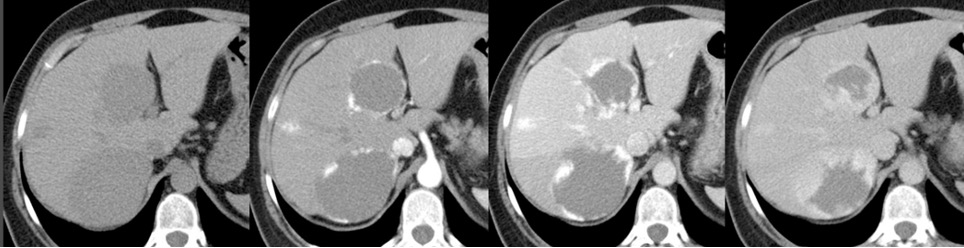

Aspetto TC

- Formazione ben definita, a margini netti, ipodensa (< 20 HU), dotata di enhancement globulare e periferico con riempimento centripeto e iperdensità tardiva.